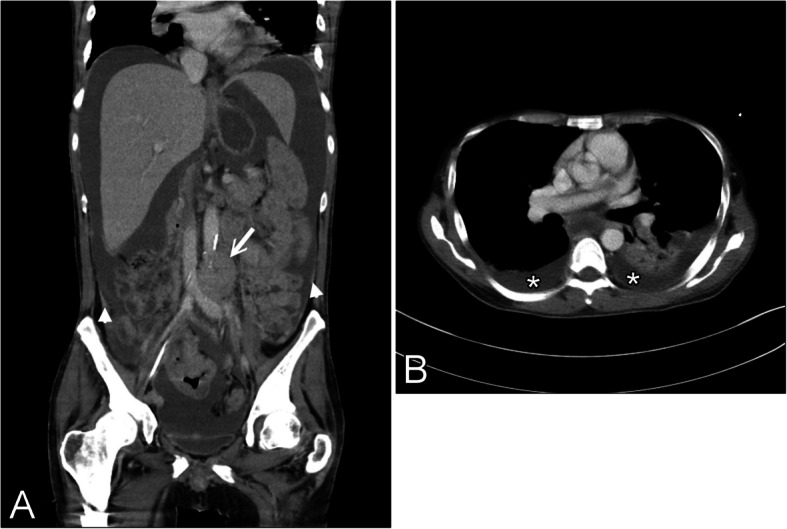

Results: We identified nine patients (four males and five females; median age 71 years). Of the eight patients tested for HIV, only one tested positive. Pathologically, the tumors showed plasmablastic morphology and immunophenotype, and three (33%) cases tested positive for Epstein-Barr virus. Six (67%) patients presented with Stage IV disease, including five (56%) with malignant effusion. Six patients were treated with chemotherapy and the remaining three received only supportive care. During a median follow-up of 10 months, five patients died of progressive disease, two died of unrelated diseases, and two were alive with PBL relapse.

Conclusion: In Taiwan, PBL constitutes a rare and aggressive clinical condition and is frequently associated with malignant effusion. In contrast to Western patients, the PBL in most patients from Taiwan was unrelated to HIV infection.